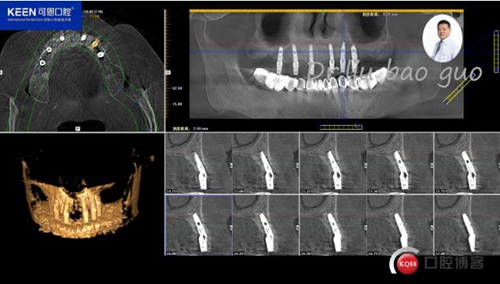

手術前種植軟件設計方案

3.jpg

4.jpg

5.jpg

6.jpg